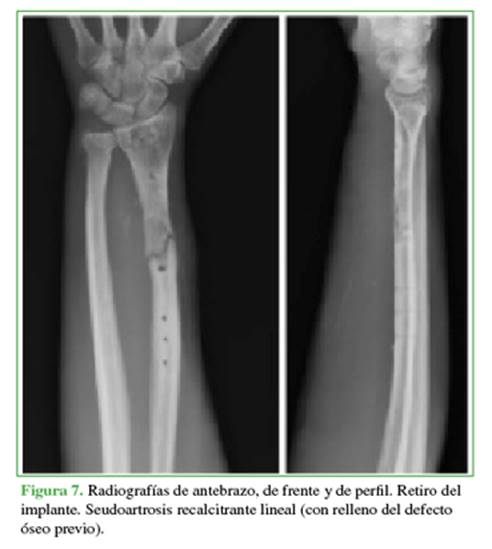

En consecuencia, se procedió a una nueva intervención para retirar el implante, explorar el foco, tomar muestras bacteriológicas y para la estabilización externa con yeso (Figura 7).